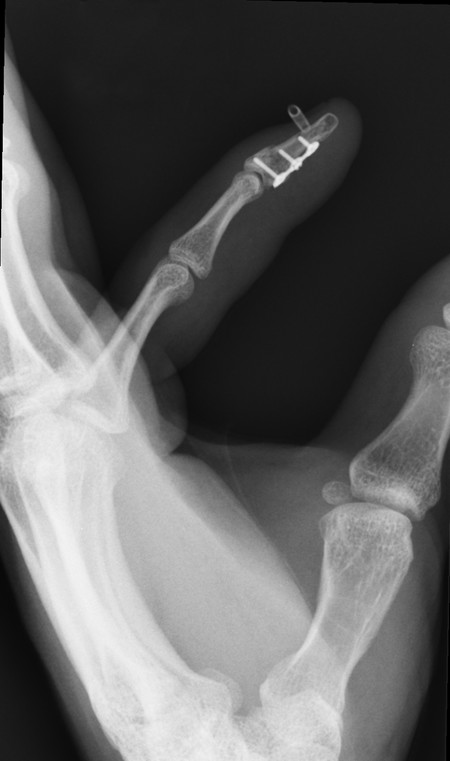

The most likely closed tendon rupture to be encountered on a hand trauma list is an FDP avulsion. The classic presentation involves the ring finger of a young rugby player who has grabbed an opponent’s shirt (jersey finger) avulsing the FDP from its insertion on the distal phalanx (Fig. 9‑8). Leddy and Packer classified these injuries into three types. In type 1, the tendon avulses from the distal phalanx and retracts to the palm, whereas in type 2, the intact vinculum longus limits retraction to the level of the proximal interphalangeal joint (PIPJ). Surgical repair of these injuries involves reinserting the FDP into the distal phalanx, which can be performed by a variety of techniques (pullout sutures, transosseous sutures, Mitek mini anchors, etc.) (Fig. 9‑9, Fig. 9‑10, Fig. 9‑11, Fig. 9‑12, Fig. 9‑13). A type 3 avulsion involves a large bony fragment attached to the FDP tendon, which is held at the distal interphalangeal joint (DIPJ) by the A5 pulley (Fig. 9‑14). These injuries can be fixed either with screws, interosseous wire fixation, or miniplate depending on the size of the bone fragment (Fig. 9‑15).

Occasionally, there can be an additional transverse fracture of the distal phalanx, which must also be fixed. This can be done either with an axial 1.1-mm K-wire, which often has to cross the DIPJ, combined with screw fixation of the fragment, or with a miniplate.